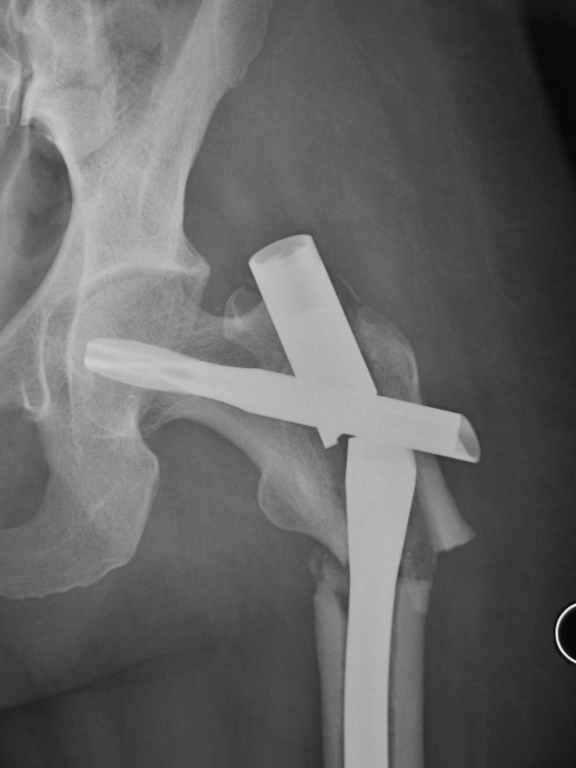

I was wondering if you could give me your thoughts on a case. 50 yo female with breast cancer who had pathologic fracture of proximal femur. Originally fixed with PFN which has broken.

Patient is a Jehovah's witness and will not take transfusions. Hgb is 8. She needs chemo for mets which are in her bladder/pelvis. How would you fix it and what would you use for bone graft? Trey

Tough case. It should have healed, I think it was the right implant.

Was it in varus to start? Too much stripping w/ the reduction?; or poor protoplasm and cancer. On the lateral it looks like the piriformis starting point was reamed w/ starting point too posterior and aiming too ant. and med. This is a common problem w/ this fx and the proximal piece ends up

flexed, ER and in varus. This may have contributed to failure, but this deformity will be the same challenge on the revision. Do you have

initial post op xrays.